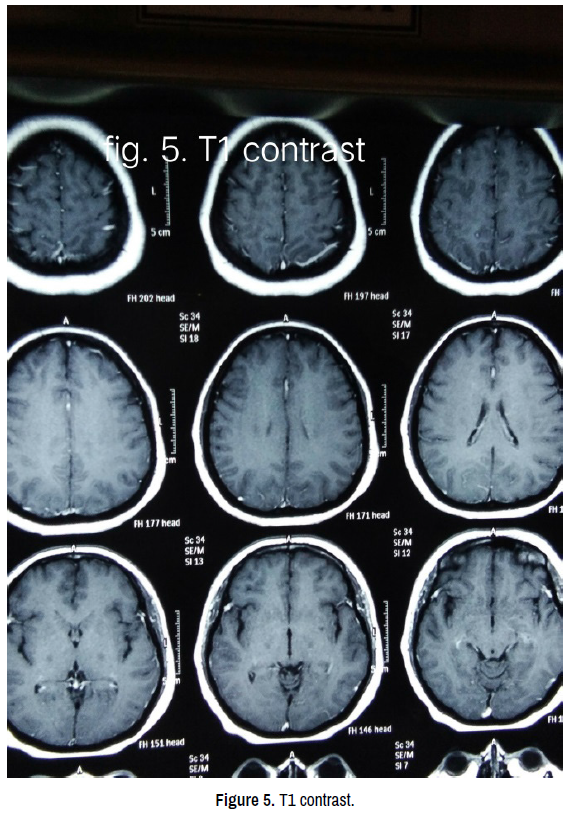

After admission she was given an intravenous infusion of labetalol which reduced her initial blood pressure to 150/90 mm Hg. Telmisartan 40 mg daily was started to control her blood pressure thereafter. MRI brain revealed bilateral hyperintense lesions in parieto-occipital and frontal cortex and watershed areas in T2 and flair images and diffusion restricted lesions in DW images (Figures 1-5). Her MR angiogram revealed multifocal vasoconstriction in cerebral arteries with diffuse beaded appearance (Figure 6). MR venogram was normal (Figure 7). EEG showed periodic bihemisheric (Rt>Lt) sharp and slow waves (Figure 2a). Her urinalysis showed mild proteinuria, sterile on culture. CBC, ESR, CRP, blood sugar, liver and kidney functions were normal.

clinical-neurology-neurosurgery-contrast

Figure 5. T1 contrast.